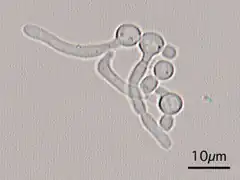

Candida Albicans Yeast forms (round-to-oval) -

Candida Albicans Hyphal forms (filamentous projections called hyphaes emerging from round-to-oval forms)